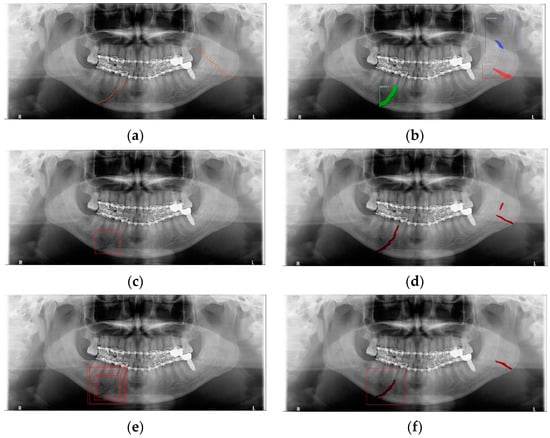

In Table 6, the parameters used for training are indicated, and in Figure 11, Figure 12 and Figure 13, the results of the doctor’s diagnosis, Mask R-CNN, YOLOv4, U-Net, LAT YOLOv4, and U-Net withYOLOv4 are compared. Figure 11 illustrates fractures in the angle and condylar regions, and in Mask R-CNN, the symphysis is misdiagnosed as a fracture. In Figure 12, the Mask R-CNN misdiagnoses the symphysis as a fracture, the result of the fact that the YOLOv4 module has better performance detecting angle fractures rather than does the LAT YOLOv4, as shown in Figure 12c,e. In short, the LAT-processed image does not always have the advantage of better revealing fractures compared with the normal panoramic radiograph.

Figure 13.

The comparison of mandibular fracture detection: (a) oral and maxillofacial radiologist, (b) Mask R-CNN (with colored polygons and boxes), (c) YOLOv4 (with a red box), (d) U-Net (with red lines), (e) LAT YOLOv4 (with red boxes), and (f) U-Net with LAT YOLOv4 (with a red box and lines).

In Figure 13, the ramus is misdiagnosed as a fracture. Therefore, Mask R-CNN had the lowest precision score because the misdiagnosis rate was higher than that of the other modules (Figure 16). The YOLO module has a low misdiagnosis rate, while the ‘undiagnosis’ rate is high; therefore, the F1 score is low owing to the ’undiagnosis’ rate. As shown in Figure 11, Figure 12 and Figure 13, YOLOv4 and LAT YOLOv4 have strong advantages over location information; therefore, they tend to detect well in the condyle region, that is, the side fracture, while they tend to detect poorly in the symphysis, body, and angle regions, where location information is ambiguous. Unlike Mask R-CNN and YOLO, U-Net is an image segmentation deep learning network, not an object detection deep learning network and labels mandibular fractures. U-Net marks fractures as lines on the label during training; however, it is difficult to label dislocated fractures, such as condyle fractures (Figure 11). Therefore, in the U-Net module, the side fracture was not diagnosed or misdiagnosed, and the precision-recall score was lower than that of the YOLO modules. It was judged that if the two deep learning networks are used together, the shortcomings of YOLO and U-Net complement each other and help improve mandibular fracture performance. In the proposed module, duplicate boxes that occurred in LAT YOLOv4 were removed before merging with the U-Net. In the proposed U-Net with LAT YOLOv4, the precision score was reduced; however, many ‘undiagnoses’ were eliminated; therefore, the recall score was increased, and it can be observed that the overall F1 score improved the performance by more than 90%.